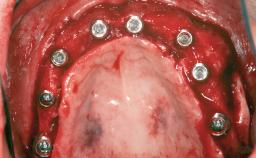

Iliac and Calvarial Bone Blocks for Onlay Grafting of a Severely Resorbed Edentulous Maxilla

# of Implants 8

Type of Implants Reduced-Diameter|Two-Piece

Bone Augmentation Horizontal|Sinus Floor Elevation|Staged|Vertical